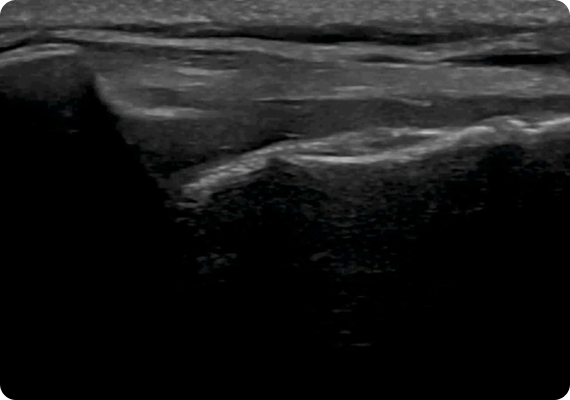

초음파 검사를 통해 쇄골 아래 흉곽출구 부위를 지나가는 신경총(Brachial Plexus)과 혈관의 압박 여부를 실시간으로 확인할 수 있습니다. 팔의 위치나 움직임에 따라 공간이 어떻게 변하는지도 관찰 가능하여, 통증이나 저림의 원인을 파악하여 치료 계획을 수립합니다.